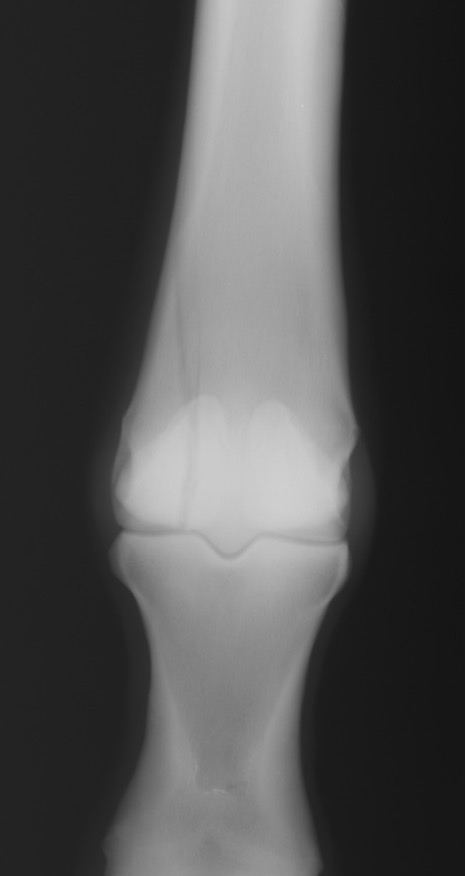

what are these fetlock fx’s

red = dorsopalmar

blue = type I prox P1 between saggital groove

green = type II wing of prox phalanx

orange = type III -basilar fx of sesamoid bones